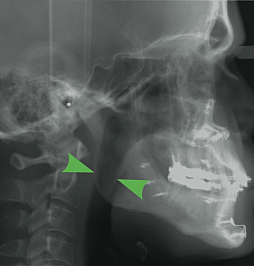

However, some individuals seek a solution for OSA which will allow them freedom from nightly CPAP or oral appliances. Dr. Bates provides surgical procedures for treatment of OSA, depending on the location of the obstruction and the severity of the apnea. Studies have shown that maxillomandibular advancement, or MMA, has the highest success rate in the treatment of severe OSA. MMA involves performing orthognathic (or “telegnathic”) surgery to make a series of cuts, or osteotomies, in the upper and lower jaws, allowing them to be separated and significantly advanced, or moved forward. Because the soft tissues in the airway which cause the obstruction, the soft palate and the tongue, are attached to the jaws, this results in a significant increase in posterior airway space which can be noticed dramatically in the before and after x-rays seen below.